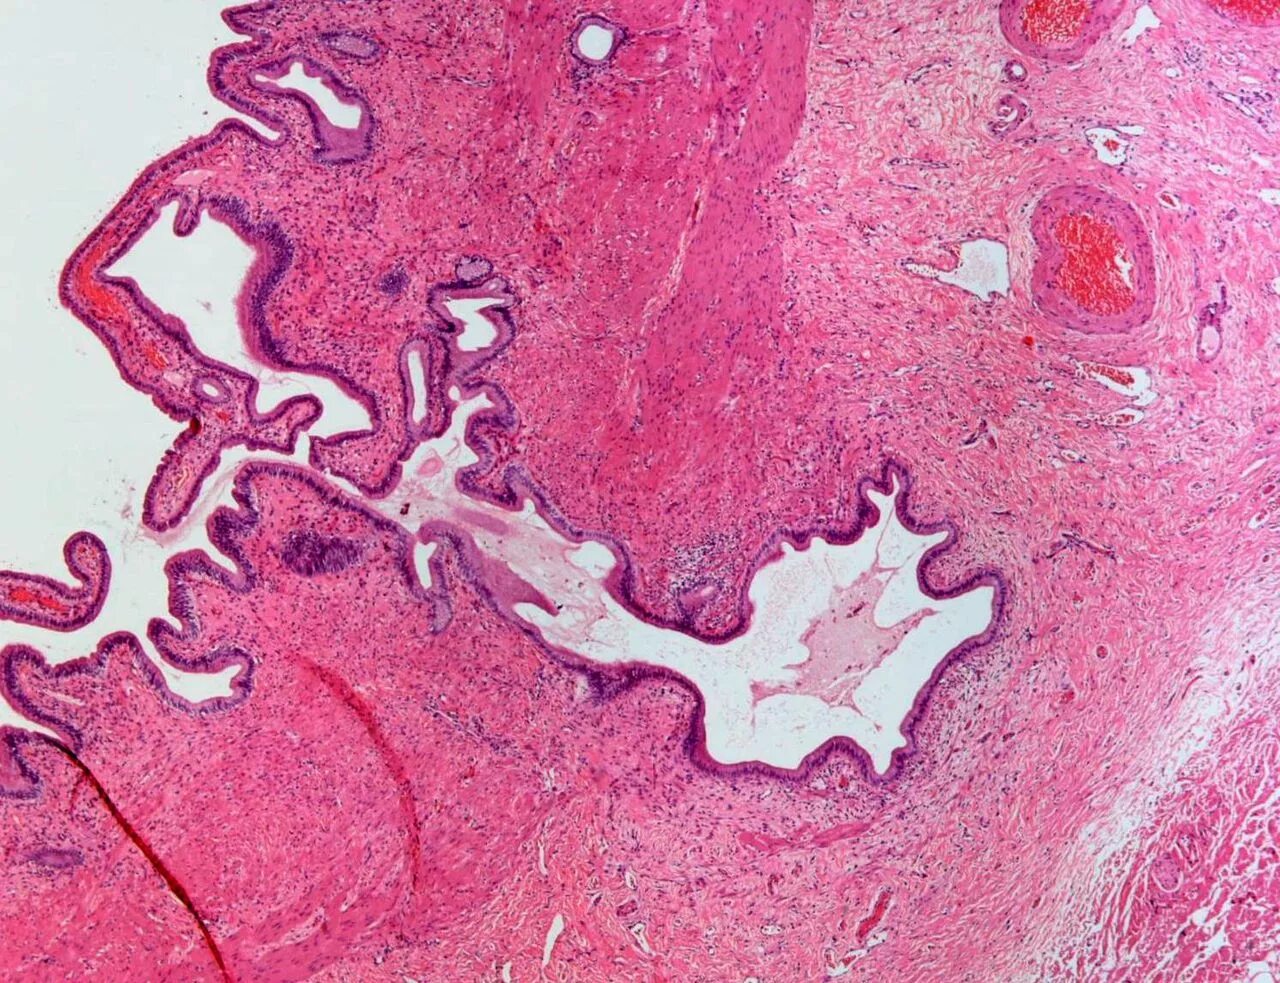

Гистологическое исследование слизистой